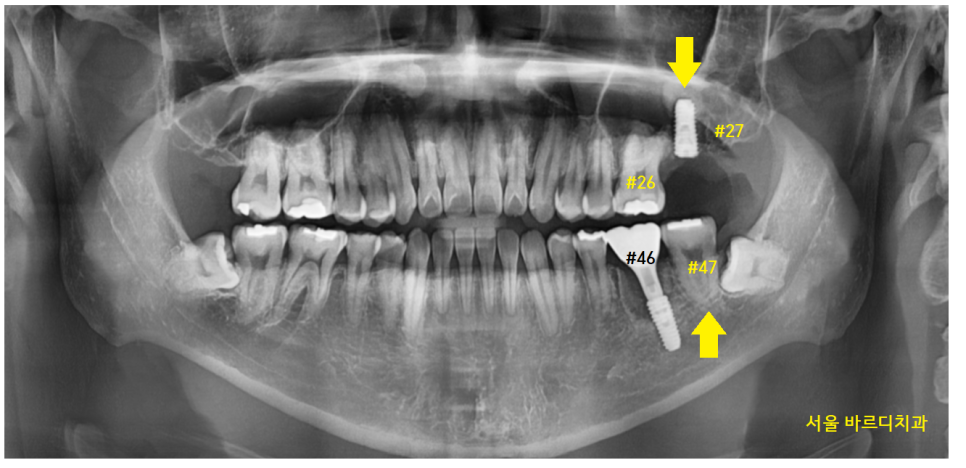

23.01.12

치아 개수가 하나가 비죠~?

오른쪽 맨 위 치아가 빠진 환자분입니다.

구강 내 사진을 보겠습니다.

#17 맨 끝 어금니가 한 개가 없네요.

이 경우에는 교합을 확인합니다.

앙~ 물어보세요.

23.03.12

#47 오른쪽 아래 맨 끝에 치아가

#16 오른쪽 제 1큰 어금니와 물리네요.

#17 맨 뒤에 치아가 없지만

물리기 때문에

이 경우는 임플란트를 안 해도 됩니다.

23.11.04

#27 맨 끝에 치아가 부러졌네요~

발치가 필요합니다.

24.02.22

아래 어금니를 지키기 위해서

발치 후 암사동 치과에서 임플란트를 식립하셨습니다.